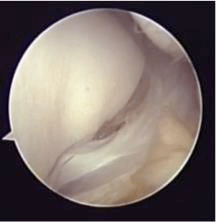

しかし、変形の強い変形性足関節症では、長期にわたり、痛みを確実に取り除くために、手術療法が必要となります。手術療法は関節固定術や関節温存手術、人工関節などがあります。我々は、リング型創外固定を使用した骨切り術による関節温存手術を積極的に行っています。末期の変形性関節症の方に対して関節固定術においても、関節鏡を用いた方法を行うことで侵襲を小さくする方法を行っています。また患者さんの状態に応じて、人工関節手術も行っています。

治療については主にギプスや装具による保存療法です。適切な治療が行われれば多くは治癒しますが、不安定性や痛みが残った場合は靭帯修復・再建術が必要になります。われわれはこの手術にも関節鏡を使用し手術を行っています。